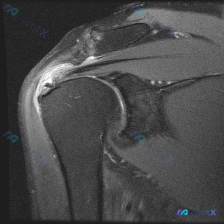

整理了一份肩部MRI病例讨论材料,医生的核心问题是排查盂唇病变,但看影像发现了一些矛盾点。先放MRI T2序列冠状位的分析: 1. 骨性结构:肱骨头、肩峰及锁骨远端轮廓尚可,未见骨折线或骨髓水肿 2. 肌腱与肩袖:冈上肌腱在肱骨大结节止点处形态异常,连续性中断,T2高信号 3. 关节与滑囊:肩峰下-...